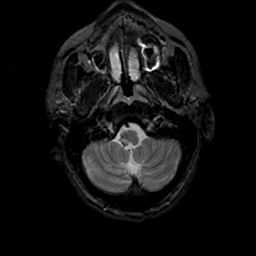

MR Study #23, January 26, 1992 -- Slice #6